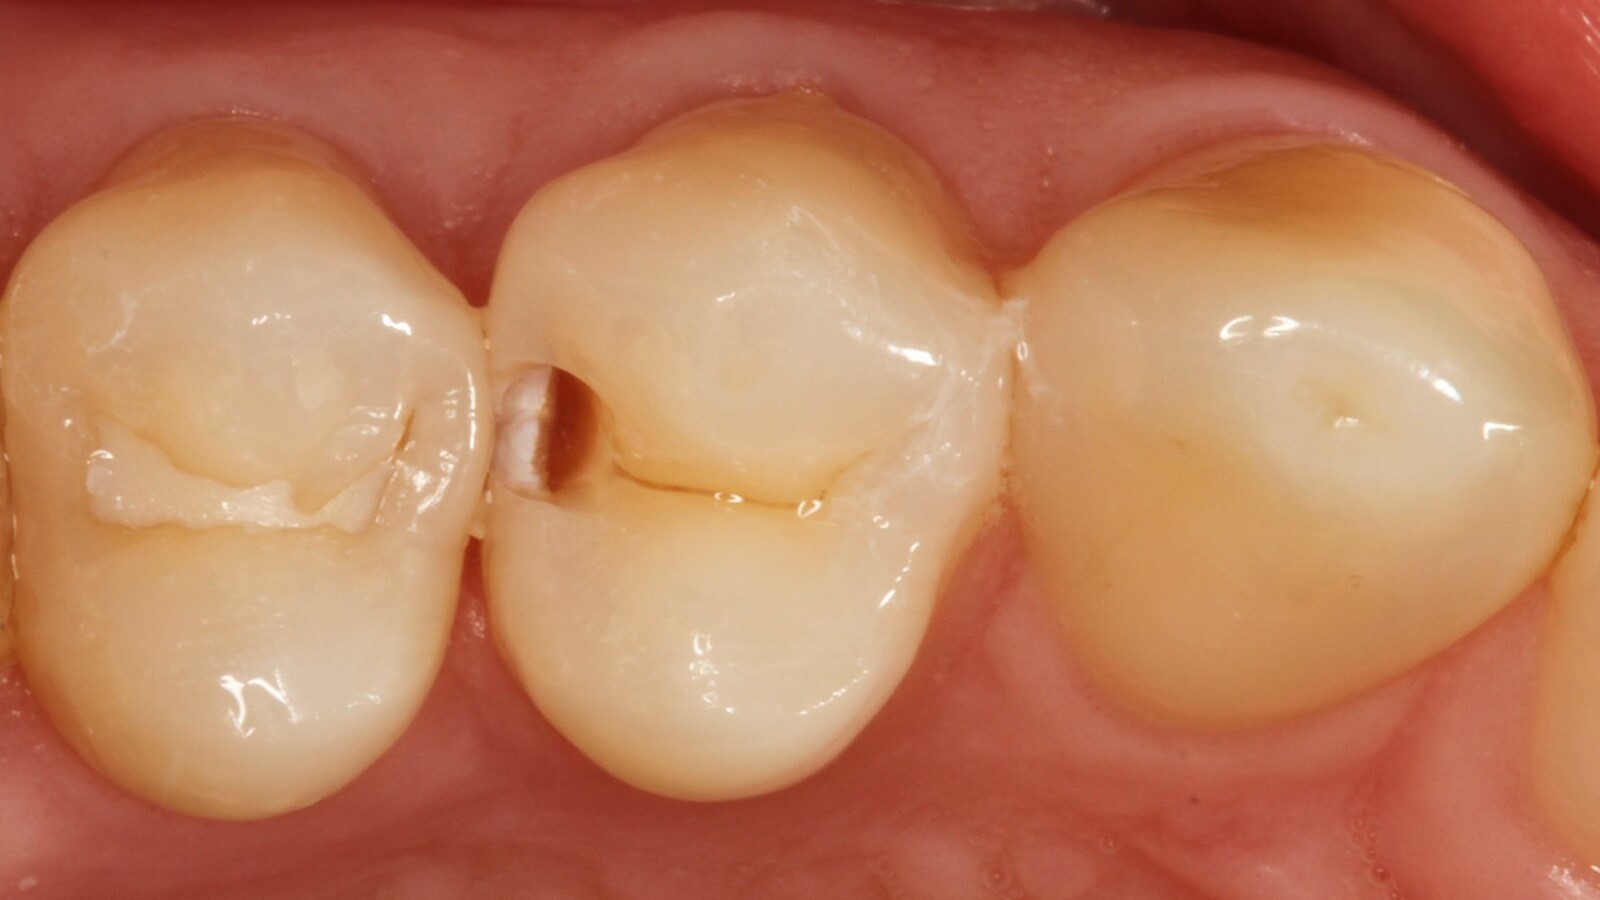

Professor Ernst first identified the hidden caries and opened the carious lesion to show the patient the problem (Fig. 1-2). He then excavated the caries, prepared the cavity and placed a sectional matrix (Fig. 3) before sealing the cavity with adhesive (Fig. 4). In a single step, he filled the cavity with Venus Bulk Flow ONE (Fig. 5). Once the restoration was completed, Prof. Ernst polished it (Fig. 6) and took a control radiograph, which also shows the excellent radiopacity of Venus Bulk Flow ONE (Fig. 7).